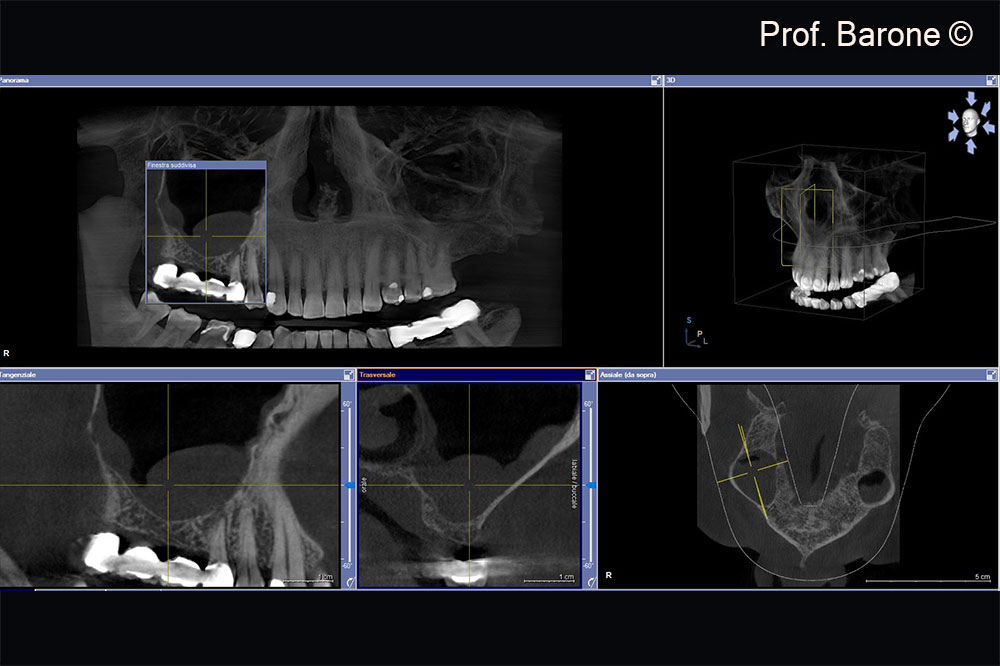

Residual ridge height doesn’t allow implant placement

Residual ridge height doesn’t allow implant placement, sinus membrane hypertrophy